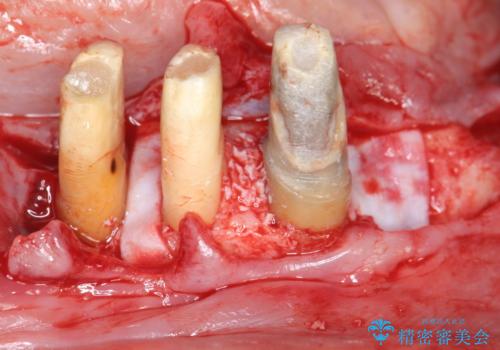

残すことのできない歯を抜去し、入れ歯になることを回避すべくブリッジ治療を行いますが支台となる歯の歯周病を改善すべく歯周病により溶けた歯槽骨の再生治療を計画します。

再生治療により良好な歯槽骨の再生が得られ、入れ歯ではなく取り外しの必要のないブリッジによる機能回復を行うことができました。